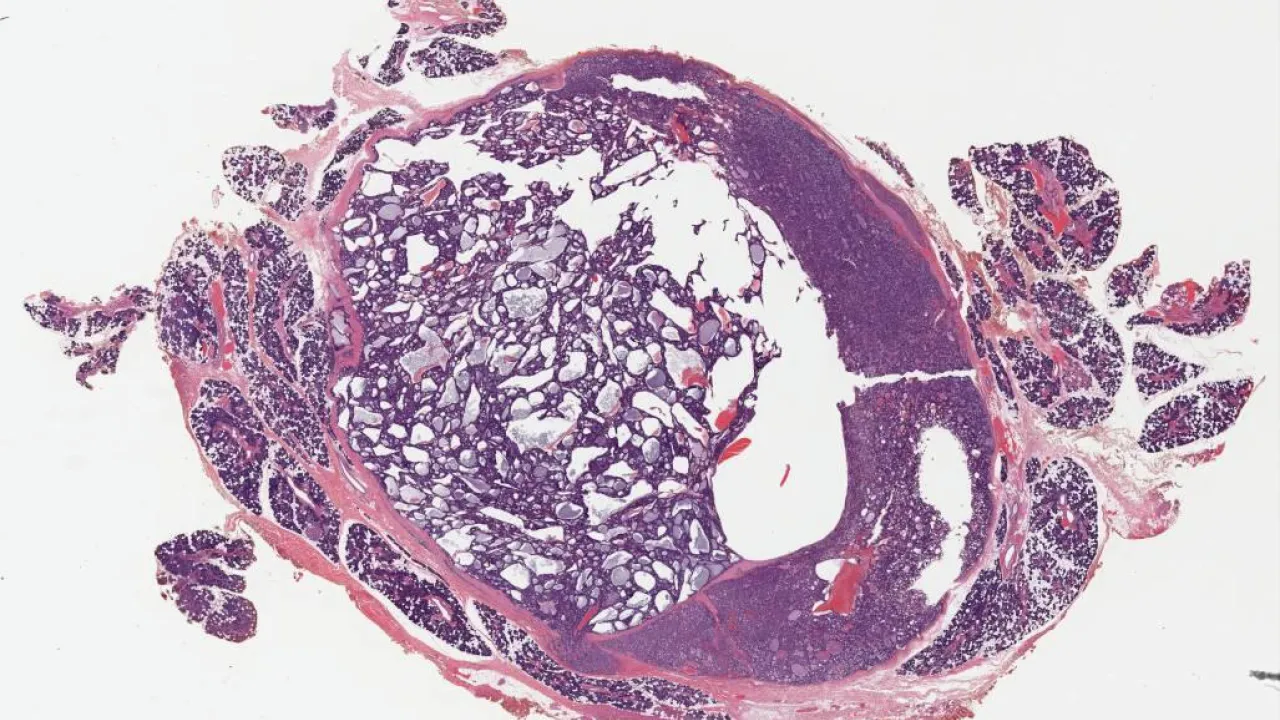

Appendix, Low grade appendiceal mucinous neoplasm